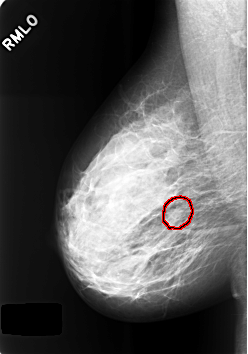

C_0421_1.RIGHT_MLO

RIGHT_MLO LINES 5664 PIXELS_PER_LINE 3960 BITS_PER_PIXEL 12 RESOLUTION 50 OVERLAY

FILE: C_0421_1.RIGHT_MLO.OVERLAY

TOTAL_ABNORMALITIES 1

ABNORMALITY 1

LESION_TYPE MASS SHAPE LOBULATED MARGINS OBSCURED

ASSESSMENT 3

SUBTLETY 3

PATHOLOGY BENIGN_WITHOUT_CALLBACK

TOTAL_OUTLINES 1

BOUNDARY